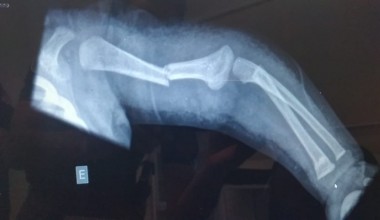

Mulher sofre fraturas expostas em acidente com moto

Acidente grave entre moto e caminhonete, mobilizou uma equipe do Corpo de Bombeiros e o SAMU. Vítima teve fraturas expostas.